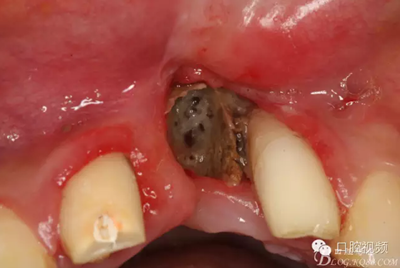

【原創(chuàng)博客】烤瓷橋下的悲劇-張東星